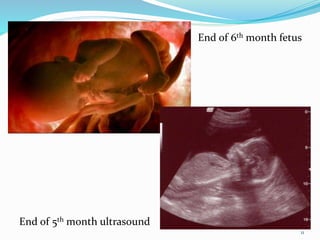

End of 5th month ultrasound

End of 6th month fetus

Second trimester

 Rapid growth occurs and the fetus is very active.

 Fetus grows rapidly about 30cm in length.

 Uterus grows sufficiently for the pregnancy to

become obvious.

 The fetal heart beat can be heard with a

stethoscope.

 Fetus moves freely through the amniotic cavity.

 5th month, the mother usually becomes aware of

fetal movements.